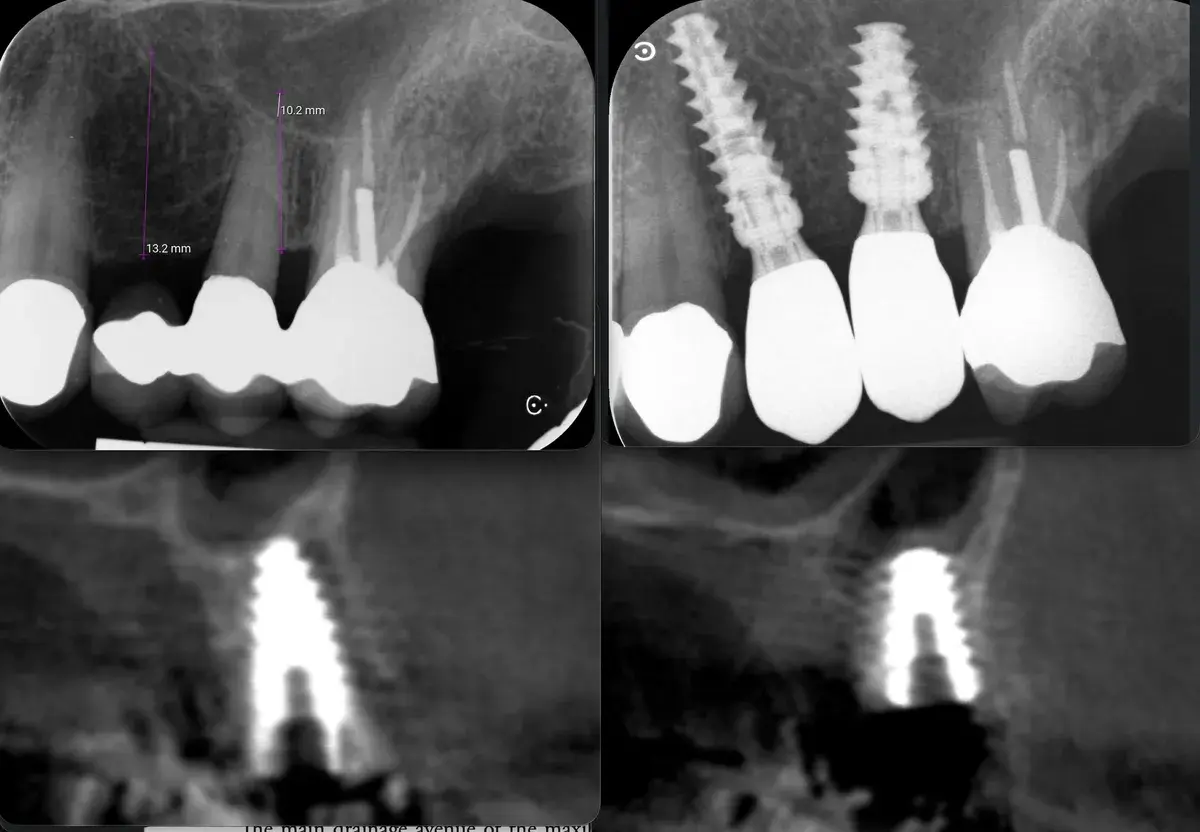

Caso clinico di sinus lift crestale immediato post-estrattivo con innesto eterologo e colla di fibrina, espansori Kalodon. Follow-up CBCT a 2 mesi.

Caso clinico di carico immediato su rialzo crestale del seno mascellare con espansori. Espansione apicale, stabilità >50 Ncm, provvisorio immediato e co...